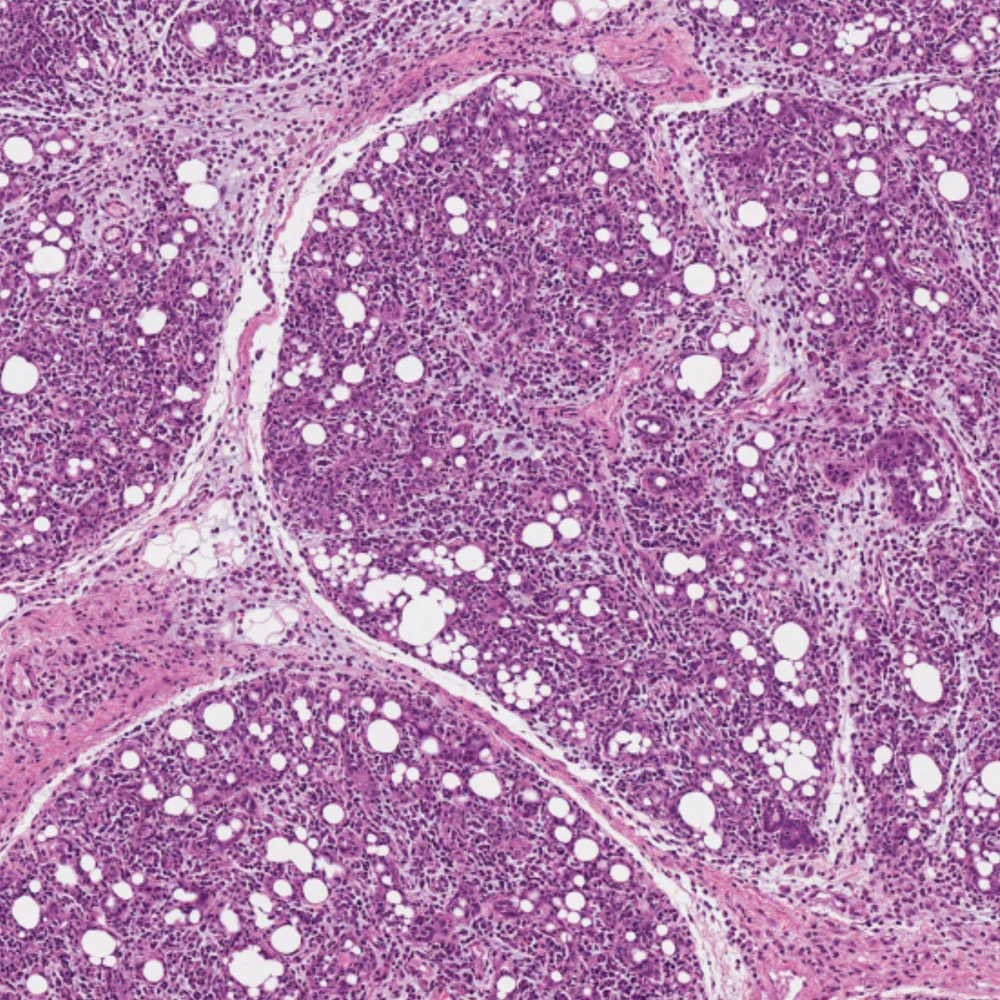

gland

I discovered that lactating mammary glands are susceptible to influenza infection. My work has been featured on the popular science shows TWIV This Week In Virology and the University of Cambridge’s The Naked Scientists.